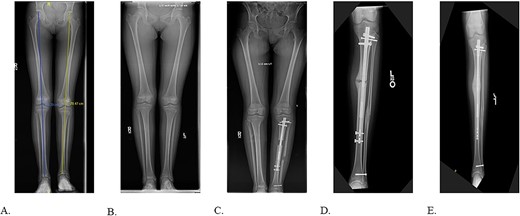

Final radiographs showed adequate alignment, internal fixation of the tibial osteotomy, and complete hardware removal aside from the three new fixation screws (Fig. 4A). The incisions were closed, dressed and the leg was immobilized in a Controlled Ankle Motion (CAM) boot. The patient spent six weeks non-weight bearing but was able to return to work without any pain or limping at three months post implant removal (Fig. 4B). Final 12-months follow-up demonstrated radiographically healed osteotomy site and maintained equal limb lengths and alignment (Fig. 5A-C).

A: 12 months postoperative PRECICE explantation with osseous union at osteotomy site of lateral left tibia. B: 12 months postoperative PRECICE explantation with osseous union at osteotomy site of AP left tibia. C: 12 months postoperative PRECICE explantation with equal limb lengths and alignment.